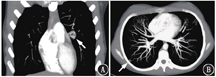

本文女性患者的肺首次通过显像可见部分肺外脏器显影,分流率为12.4%——在阳性界值边缘,这该如何判读结果呢?在计算分流率时,99Tcm-MAA的标记率、胶体产生等技术因素会影响图像和分流率计算,但游离锝、胶体等不能穿过血脑屏障,所以如果脑内出现摄取,就说明99Tcm-MAA分布在脑组织中,而不是其他因素导致的,这一征象对判断右向左的解剖分流有很高的特异性[3]。Sugiyama等[7]的研究中,2例肺动静脉瘘患者治疗前分流率低于15%,但可见脑内摄取,提示存在比较小的分流;在成功进行栓塞术后,分流率并无明显变化,但脑内的异常摄取消失。这提示99Tcm-MAA显像中脑内摄取对判断右向左分流更灵敏、特异。本文女性患者99Tcm-MAA肺首次通过显像可见脑显影,甲状腺、脾、双肾、肠道亦见显影,高度提示存在右向左的解剖分流。患者之后行CTPA,可见双肺多发动静脉瘘,较大者位于左肺上叶舌段(图2)。